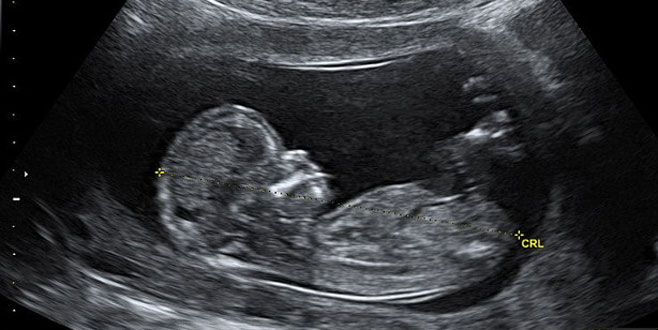

Hamilelikte cinsiyet ne zaman belli olur. Bebeğin cinsiyeti ne zaman belli olur. Erken gebelik dönemlerinde bebek cinsiyet hesaplamaları bakılan ultrasonografi cihazının gelişmişliğiyle de alakalıdır. Hamilelik döneminde bebeğin cinsiyetini belirlemek için ultrason muayenesi yapılır. Hamile kalmakla ilgili en zor şeylerden biri bebeğinizin bir erkek veya bir kız olup olmadığını merak etmek.

Hamilelik döneminde bebeğin cinsiyeti öğrenebilmek umudu ile anne adayına ultrason muayenesi yapılır. Bebek cinsiyeti ne zaman belli olur. Bebek cinsiyeti ne zaman belli olur. Kısmen de olsa 13 16.

Anne karnındaki bebeğin cinsiyeti kaçınca haftada belli olur. Hamilelik döneminde bebeğin cinsiyetinin ne olduğu çok merak edilir. Annenin hamilelik süresince en çok merak. Haftada cinsiyet görülebilse de en kesin sonuç 20.